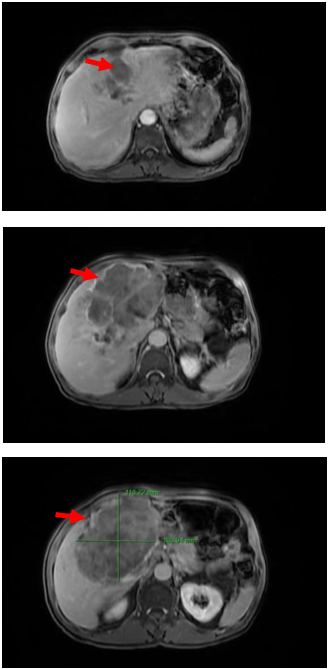

- Cộng hưởng từ ổ bụng: Nhu mô gan 2 bên có vài khối nốt tổn thương, lớn nhất vị trí rốn gan kích thước 105x140x132mm, bờ không đều, giảm tín hiệu trên T1W, có phần tăng tín hiệu trên T1W dạng chảy máu, tăng nhẹ không đồng nhất trên T2W, hạn chế khuếch tán trên DWI/ADC, sau tiêm ngấm thuốc ở ngoai vi thì động mạch, ngấm thuốc lan dần vào trung tâm thì muộn, thì gan mật không giữ thuốc. Tổn thương xâm lấn đè đẩy hạn chế đánh giá nhánh trái TMC, đè đẩy hẹp thân chung TMC

Hình ảnh chụp Cộng hưởng từ có tiêm thuốc đối quang từ (T1W): Vị trí các khối u theo hướng chỉ của mũi tên đỏ